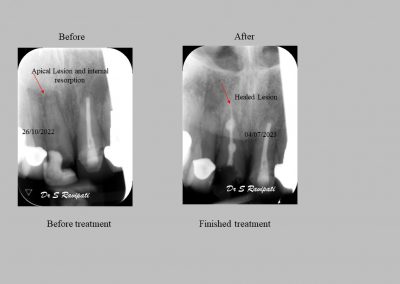

During the consultation, the dentist will first listen to your concerns and carry out appropriate tests to identify the right tooth that is causing pain. As a part of the diagnosis, your dentist will carry out various clinical tests to identify the right tooth and will take some radiographs which can aid in the diagnosis.

Files of different sizes are used to eliminate bacteria and infection and to shape the canals. The canals are disinfected thoroughly with irrigants and later the canals will be sealed in 3 dimensions with a special medicament called gutta-percha to prevent reinfection of the tooth and the access cavity will be sealed with a temporary filling.

Studies have shown thorough cleaning with instruments, disinfection and sealing the canals contribute to the successful healing of the infection and this success is reported as 95%.